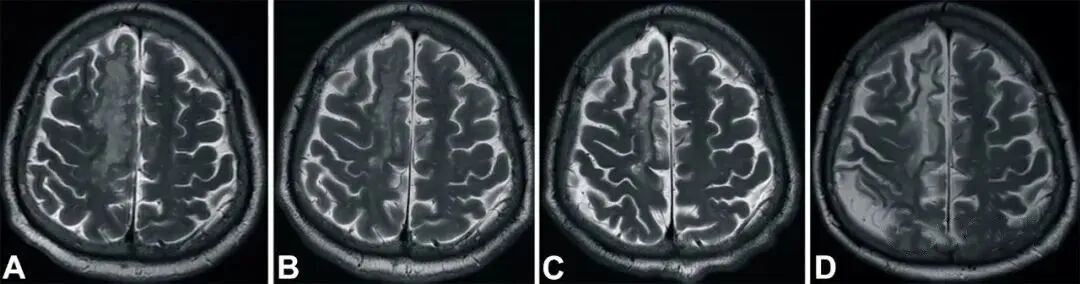

2019年,研究人员在《干细胞转化医学》(Stem Cells Translational Medicine)杂志上公布,干细胞有助于脑卒中偏瘫患者运动功能的恢复。9名年龄在30至65岁之间的偏瘫患者参与了这项临床研究,他们在中风后5-24个月接受干细胞脑内治疗,干细胞被注射至脑内梗塞灶附近。结果表明,干细胞治疗偏瘫性脑卒中拥有一定的临床益处。